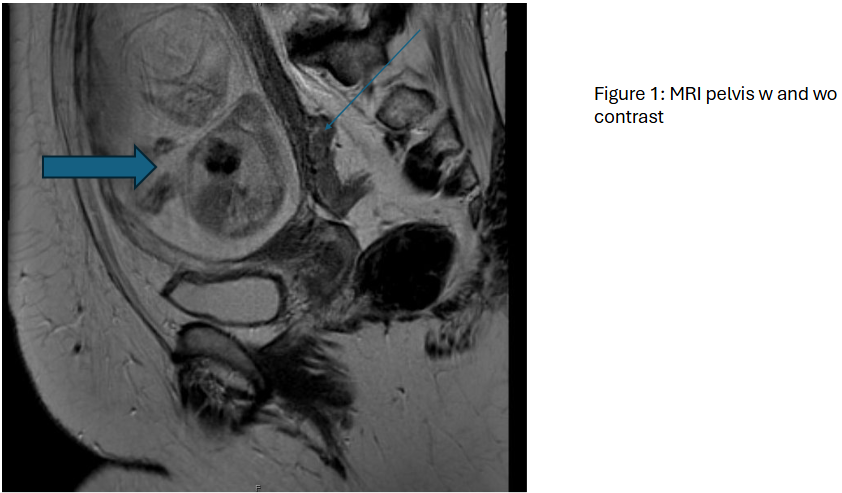

Caption; MRI pelvis, thin blue arrow represents rectal mass, thick blue arrow represents fetus.

Histologic sections show residual adenocarcinoma (C) invading through the muscularis propria and into the pericolorectal tissue (A-B). Two separate tumor deposits were identified (D).